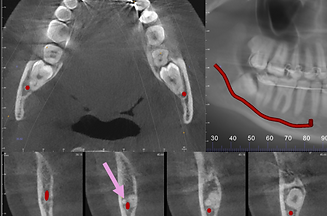

Cross-sectional images, IAN tracing and alveolar ridge measurements for implant planning at site #19.

Incidental finding: Internal root resorption at tooth #9 (arrows)

Right IAN courses through the apical third of the roots of impacted #32.